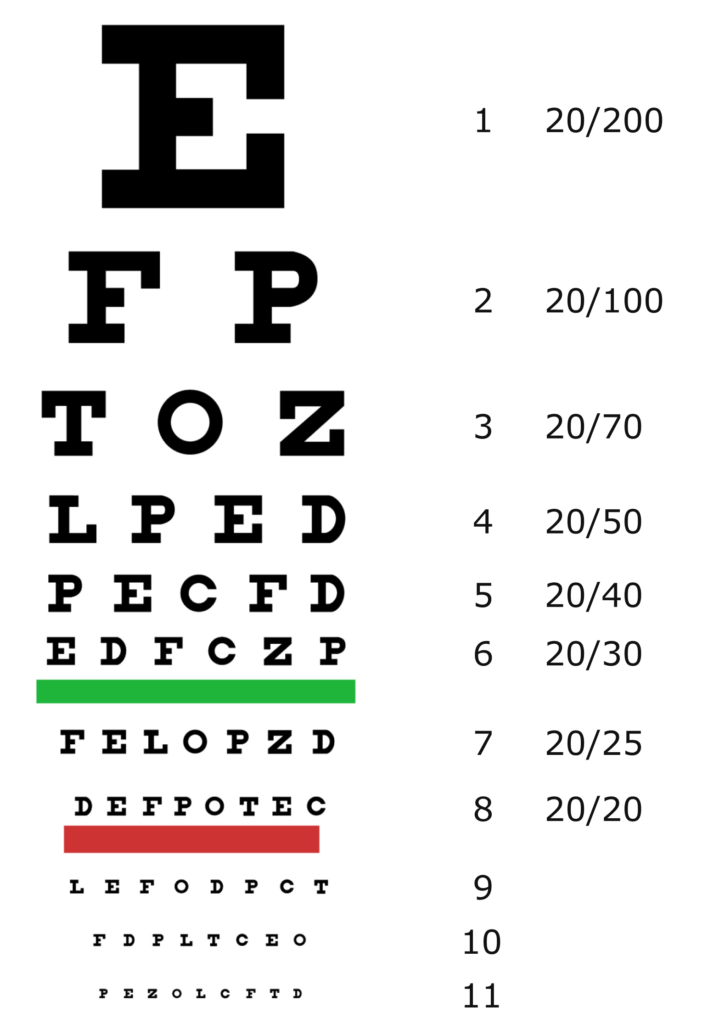

Exame oftalmológico completo

O principal sintoma apresentado por pessoas com DMRI é a perda de visão. Dessa forma, a DMRI costuma ser diagnosticada em exames oftalmológicos de rotina, que avaliam a acuidade visual – ou seja, a capacidade de ver detalhes, formas e letras a uma certa distância.4 Isso normalmente é avaliado usando a chamada tabela de Snellen, embora outras tabelas também possam ser usadas. O número de letras que uma pessoa consegue identificar corretamente (ou seja, quanto mais abaixo ela consegue ler na tabela) representa sua acuidade visual.4